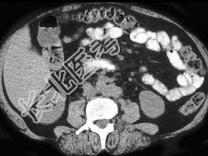

- 单项选择题根据皮下组织的表现,该病例可能性最大的诊断为 ( )

A、转移

B、淋巴瘤

C、良性囊肿

D、黑色素瘤

E、纤维瘤